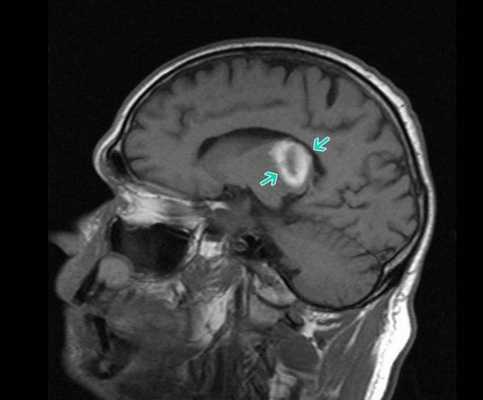

Липома четверохолмной цистерны на МРТ (обведена кругом)

Абсцесс головного мозга на МРТ (указан стрелкой)

Опухоль головного мозга на МРТ (указана стрелкой)

Лакунарный инфаркт головного мозга на МРТ (указан стрелкой)